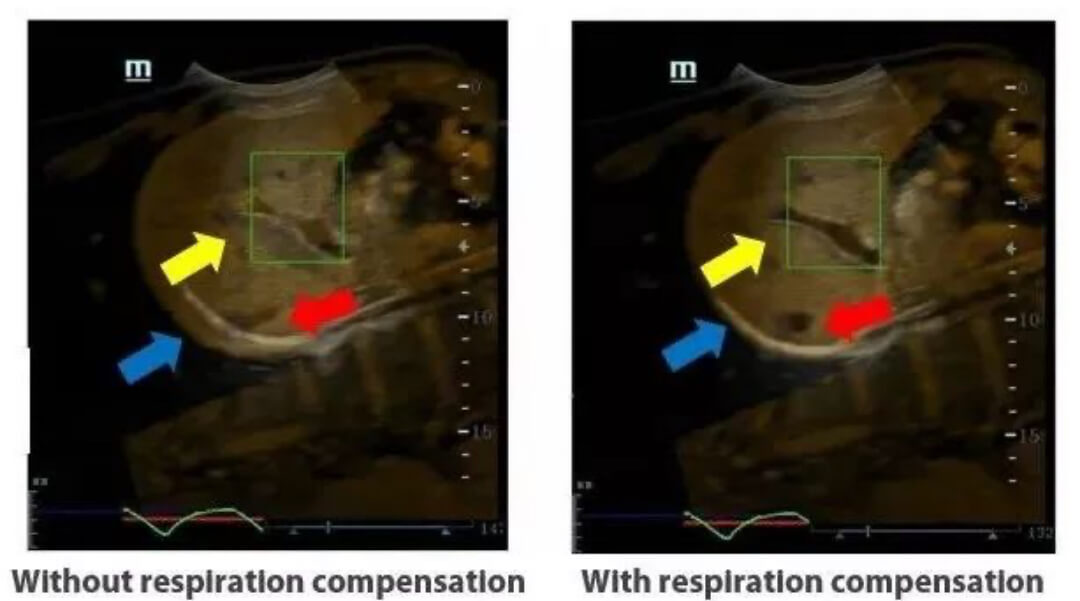

Despite of obvious advantages of fusion imaging, the inevitable respiratory motion of the patient which decreases the accuracy of fusion, remains a big clinical challenge.

To address such clinical challenge, Mindray rolls out its innovative and exclusive respiration compensation technology, supported by a sensitive magnetic motion sensor with millimeter accuracy, aiming to help eliminate distortion and fusion inaccuracy caused by patient respiration.

It has been proved in clinical experiments that Mindray's iFusion can correct approximately 80%[1] of fusion errors caused by respiratory motion and markedly improve the fusion accuracy of a full respiration cycle.

The innovative and patented Mindray technology, iFusion, provides remarkable clinical values by remedying the respiration-induced artifact e?ectively. As a result, it renders more con?dence to clinicians on diagnosing intractable lesions as well as conducting interventional therapy, markedly improving the accuracy of fusion imaging to a new level.